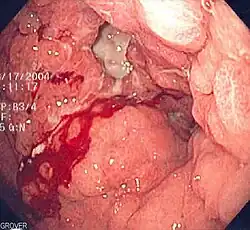

- Zichtbaar bloedverlies. Sommigen zullen dit geen inwendige bloeding meer noemen. Abnormaal bloedverlies is altijd een reden voor medisch onderzoek naar de oorzaak. Het bloedverlies zelf is echter lang niet altijd spoedeisend. Een neusbloeding kan er indrukwekkend uitzien, maar meestal is het probleem te verhelpen door een paar minuten de neusvleugels tegen elkaar te duwen. Bloedverlies bij de urine is zelden spoedeisend; een paar druppels bloed kleuren een grote hoeveelheid urine rood, waardoor het erger lijkt dan het is, al zal de arts wel grondig willen uitzoeken waar het vandaan komt. Bloed uit de longen is schuimend en rose. Meestal is het niet de hoeveelheid bloed maar de toestand van de longen zelf die aandacht nodig heeft. Bloedverlies uit de maag is meestal zwart door de inwerking van het maagzuur. Donker braken of zwarte ontlasting kunnen wijzen op grote, gevaarlijke hoeveelheden bloedverlies. Na een bevalling kunnen vrouwen gevaarlijke hoeveelheden bloed verliezen (fluxus post partum), bijvoorbeeld als de placenta niet geheel losgekomen is of als de baarmoeder niet goed samentrekt.

- De gezondheid van het weefsel. Zowel kanker als ontstekingen bloeden gauw en gemakkelijk.